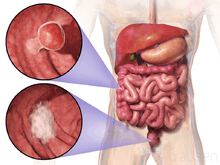

Cancers on the right side of the large intestine (ascending colon and cecum) tend to be exophytic, that is, the tumor grows outwards from one location in the bowel wall. This very rarely causes obstruction of feces, and presents with symptoms such as anemia. Left-sided tumors tend to be circumferential, and can obstruct the bowel lumen, much like a napkin ring, and results in thinner caliber stools.

Appearance of the inside of the colon showing one invasive colorectal carcinoma (the crater-like, reddish, irregularly shaped tumor)

Appearance of the inside of the colon showing one invasive colorectal carcinoma (the crater-like, reddish, irregularly shaped tumor) Gross appearance of a colectomy specimen containing two adenomatous polyps (the brownish oval tumors above the labels, attached to the normal beige lining by a stalk) and one invasive colorectal carcinoma (the crater-like, reddish, irregularly shaped tumor located above the label)

Gross appearance of a colectomy specimen containing two adenomatous polyps (the brownish oval tumors above the labels, attached to the normal beige lining by a stalk) and one invasive colorectal carcinoma (the crater-like, reddish, irregularly shaped tumor located above the label) Endoscopic image of colon cancer identified in sigmoid colon on screening colonoscopy in the setting of Crohn's disease